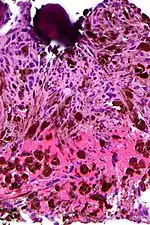

Micrograph of psammoma body in the centre of the field in a meningioma of brain. H&E stain.

A psammoma body is a round collection of calcium, seen microscopically. The term is derived from Greek άμμος (ámmos) 'sand'.

Psammoma bodies usually have a laminar appearance, are circular, acellular and basophilic.